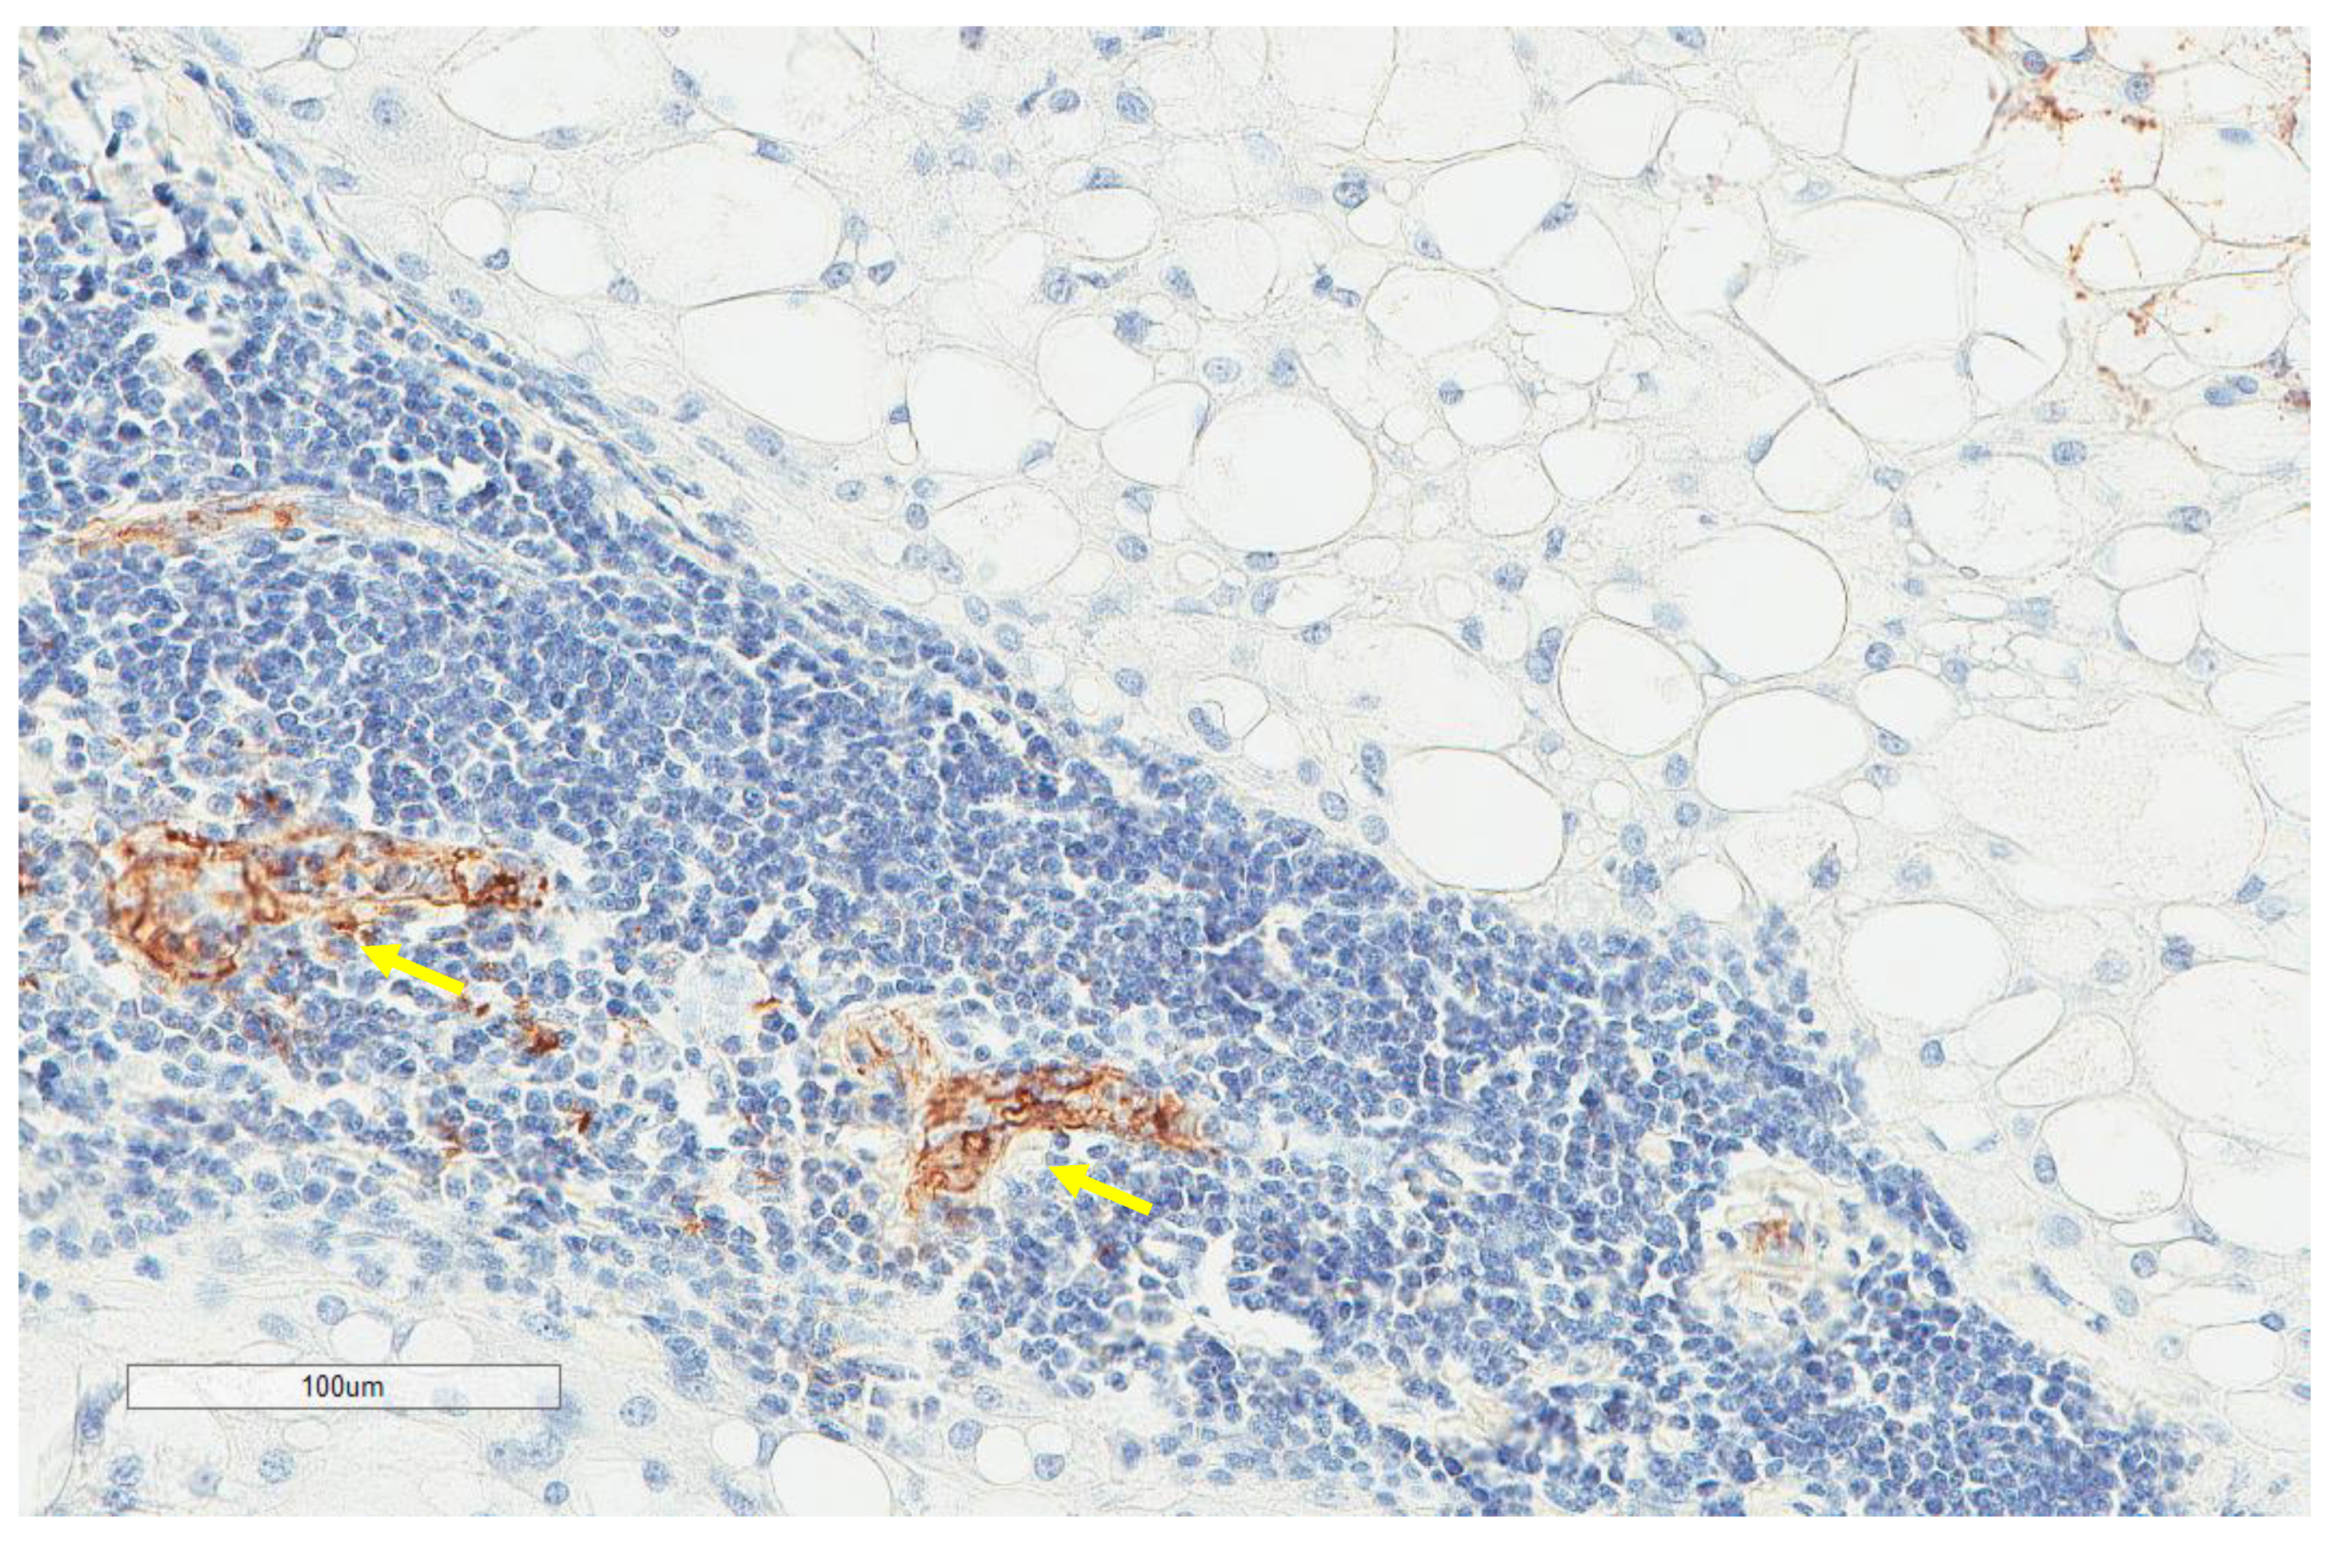

| MECA-79 vessels (n = 59) | |

| High | 5, 8.5% |

| Low | 54, 91.5% |